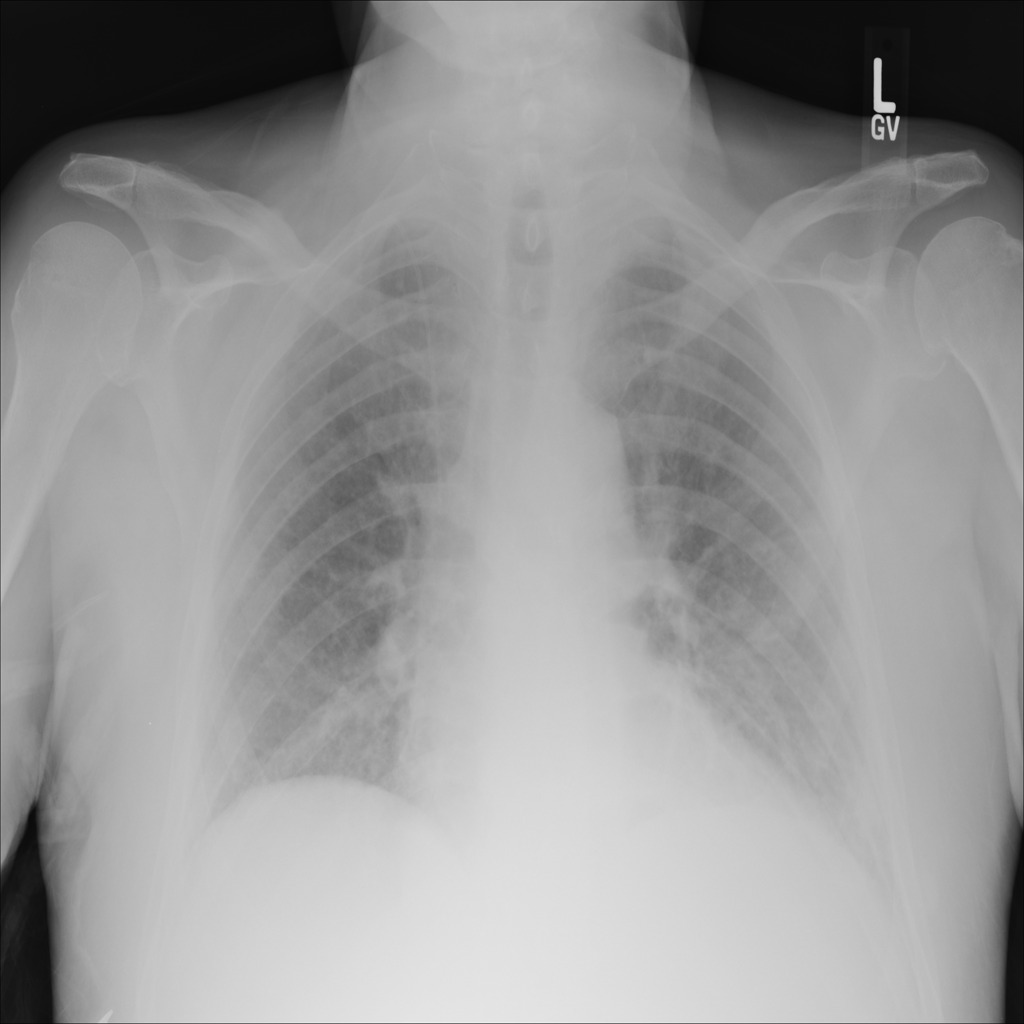

PAT-5B86 · IMG-009Edema

PAT-5B86 · IMG-009

PA